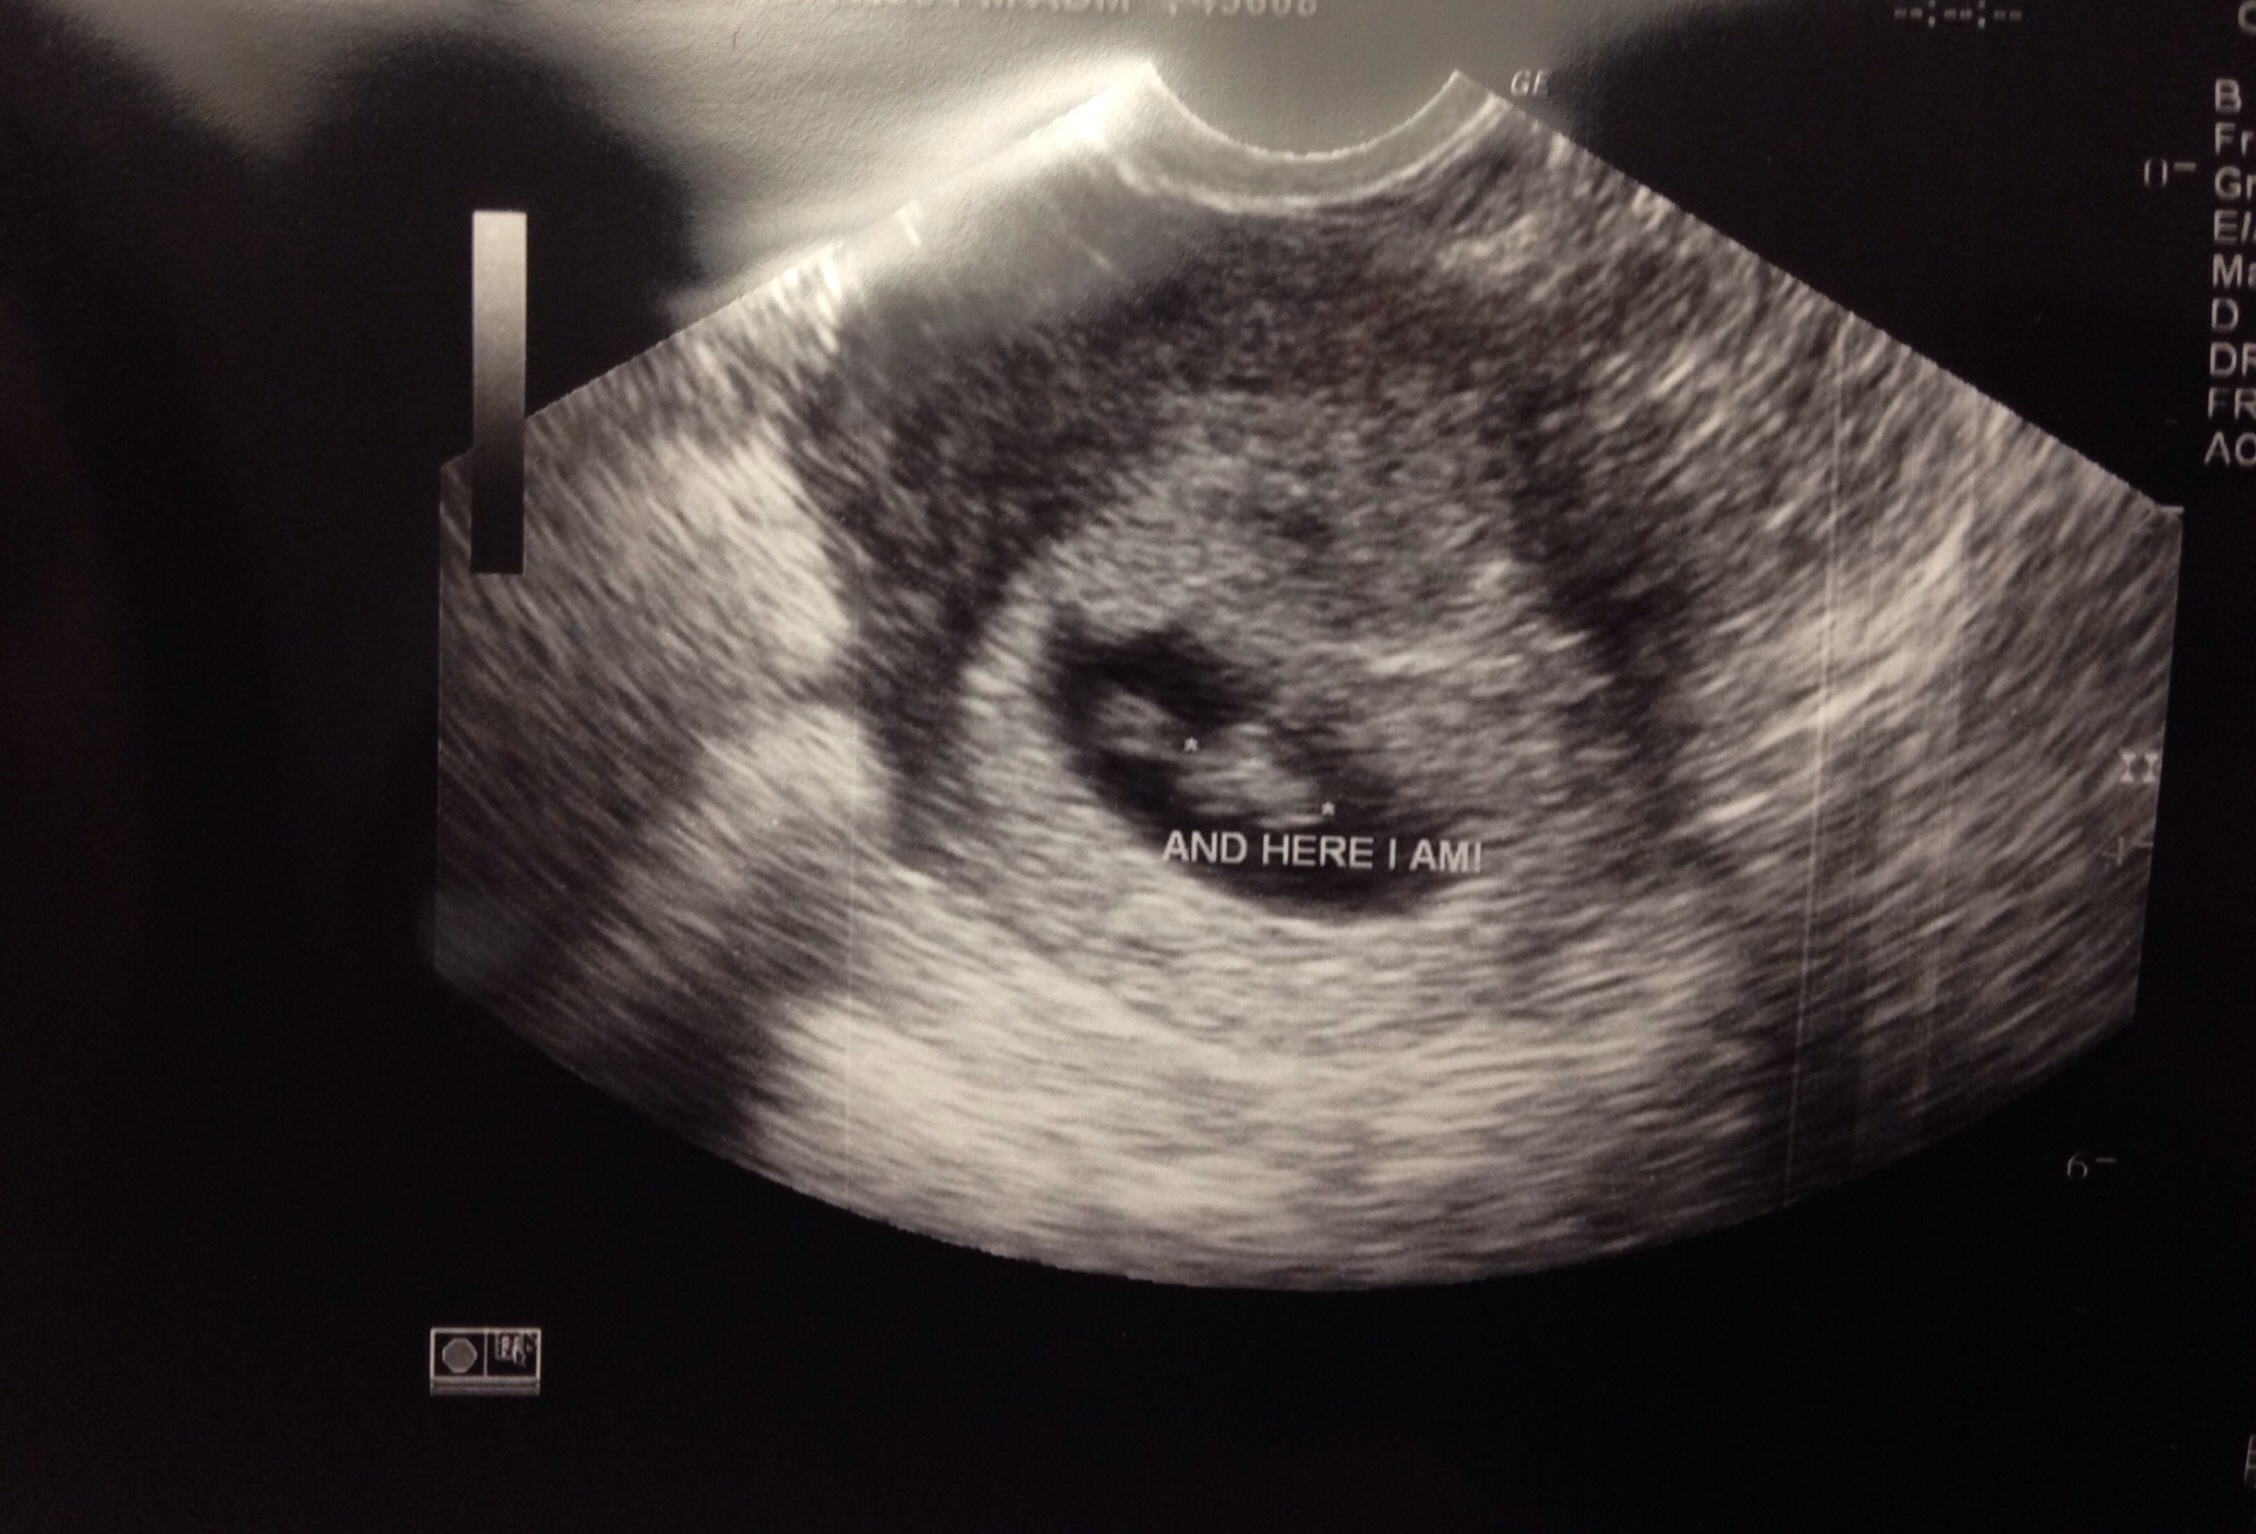

• I'm 7 weeks 2 days. Could one of the corpus luteum have absorbed? Do we agree it's two sacs? Definitely two placenta but doctor was weary to say "two sacs" since he said it was early and lining could thin. But goodness they sure do look like two separate sacs

• Where is the placenta? Now I'm confused if he showed me the two babies and two yolk sacs.. :-/